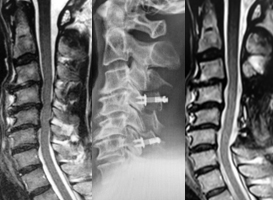

頚椎椎弓形成術の代表的な手術法に、片開き式脊柱管拡大術があります。ご高齢の方に対しても、安全で安定した成績が報告されている優れた術式です。手術は首の後ろを切開して、椎弓の両側に骨の溝を掘り、扉を開くように脊柱管を拡大します。開いた椎弓は再度閉じないように糸で固定したり、金属性のプレートで固定します。通常、手術翌日より座位や歩行訓練を行います。手術後のカラーは、病態により装着を考慮します。

(左)術前のMRIでは、全体的に脊柱管内の狭窄があります。(中)片開き式脊柱管拡大術を施行し、金属性のプレートで椎弓を固定しています。(右)手術により脊柱管が拡大され、神経症状が改善しています。